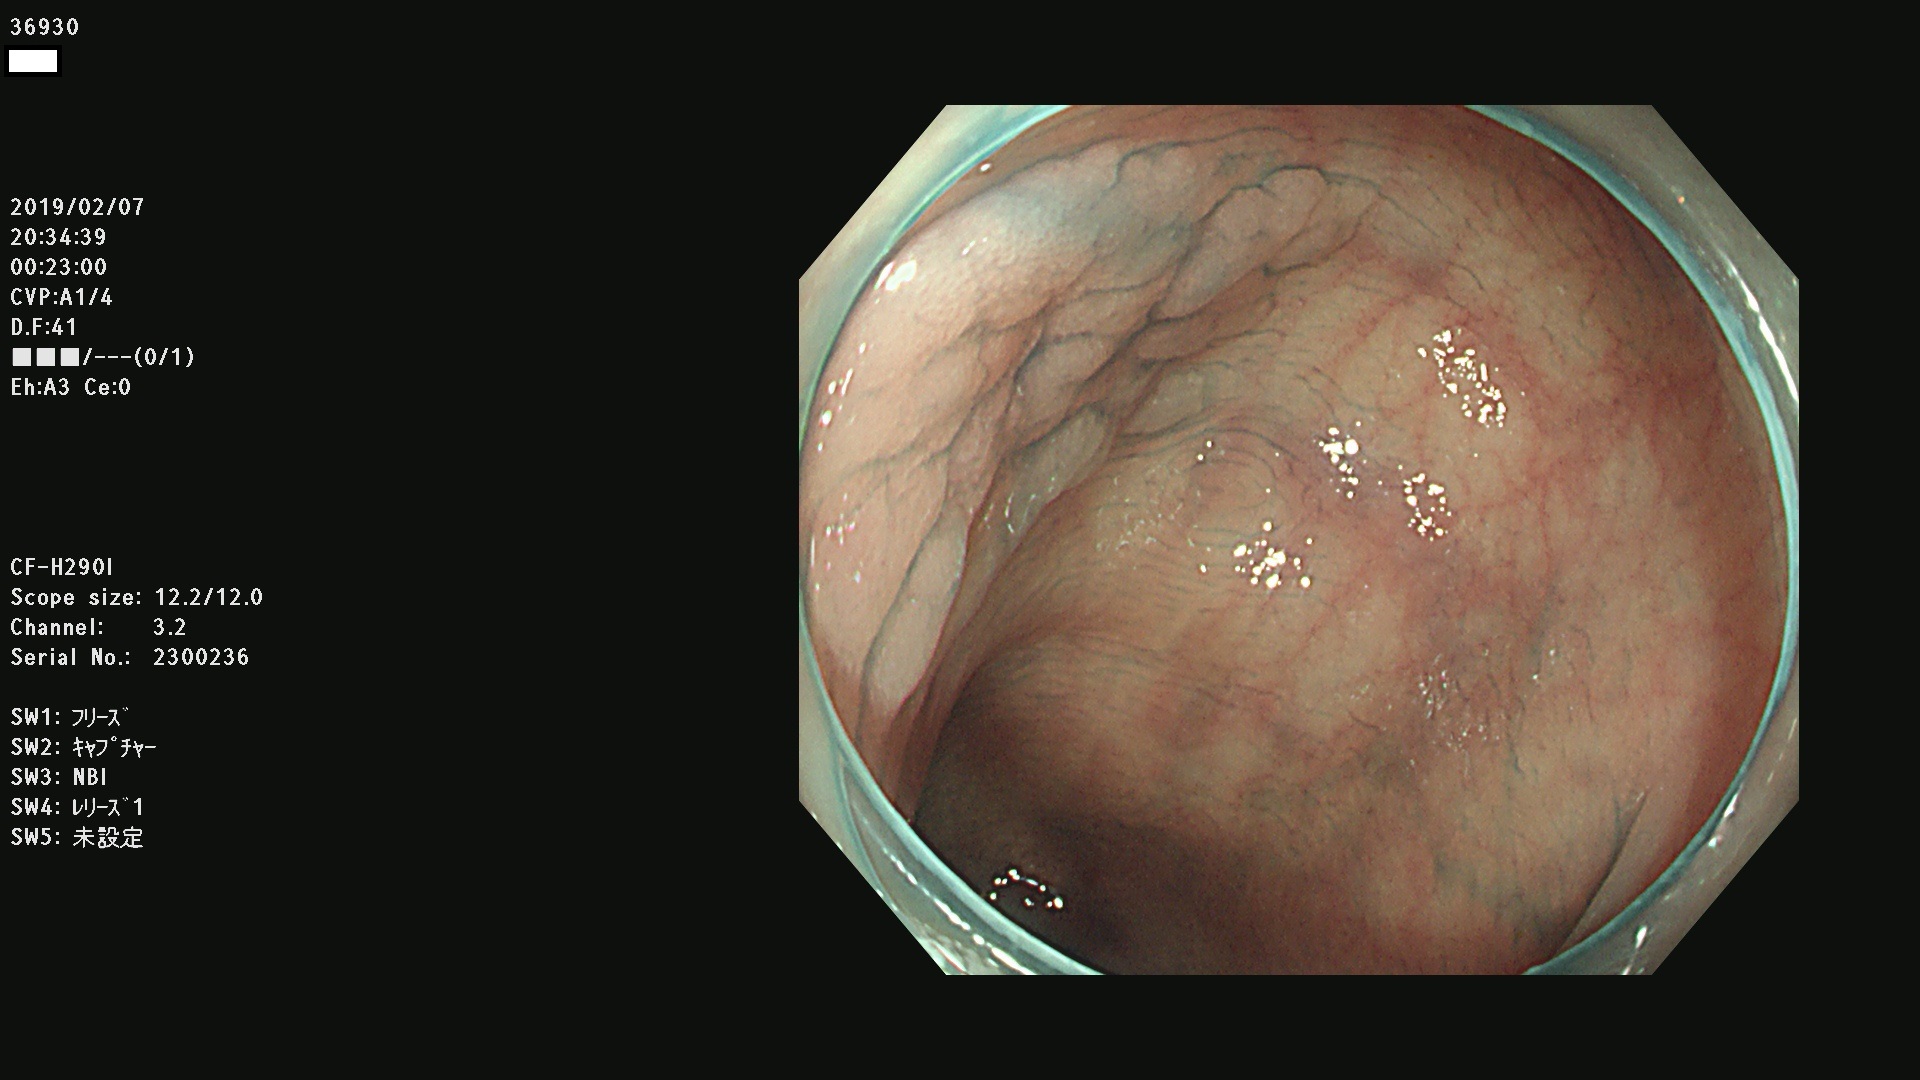

腺腫発見率 67 % (カルテ番号 36900〜36999の100名の方の検査結果で集計)大腸癌検診最新情報

以下のカルテ番号の方に腺腫(Adenoma,Group3〜5)が見つかりました(集計法)

36900 36901 36903 36904 36905 36908 36909 36910 36911 36913 36914 36915 36916 36917 36918 36919 36920 36923 36924 36925 36927 36928 36930 36931(SSAPのみ) 36933 36935 36936 36937 36941 36943 36944 36945 36946 36949 36951 36953 36954 36955 36957 36963 36965 36966 36967 36968 36969 36970 36974 36975 36976 36977 36978 36979 36980 36981 36983 36984 36986 36987 36988 36989 36990 36991 36993 36994 36996 36998 36999

発見困難で危険性の高い平坦型病変(上記100名より抽出) ![]()